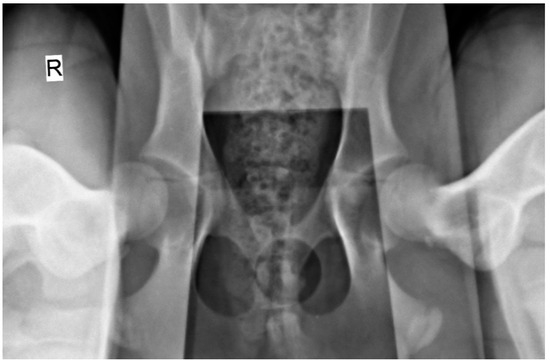

2.2. Radiographic Hip Stress View and Hip Laxity Measurement